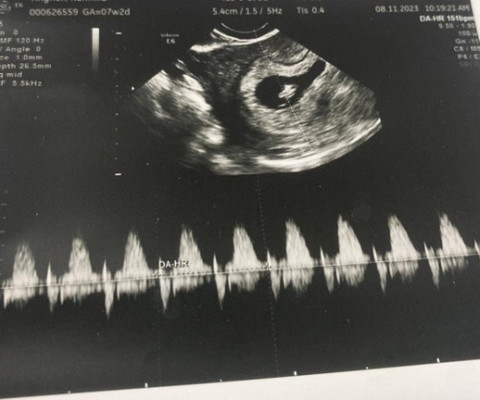

ไปฝากท้อง7w เจอน้องด้วยค่ะ

ดีใจมากเลยตอนแรกกังวลจะไม่เจอตัวน้อง แต่อัลตร้าซาวด์ทางช่องคลอดนะคะ เห็นหัวใจน้องเต้นด้วย ใจฟูมากค่ะ

ใช่ค่ะได้ยินเสียงหัวใจลูกน้ำตาจะไหลออกมาเลยค่ะแม่